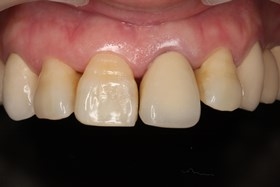

- 治療前全口X光片、口內正面照片。

治療前全口X光片、口內正面照片